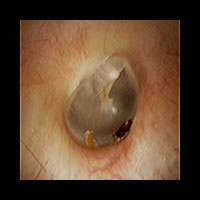

右急性中耳炎(中等症)

鼓膜がやや赤くなっています。鼓膜の奥に膿が透けて見えています。鼓膜の腫れはありません。抗生剤の内服で鼓膜切開を行わずに16日目で治りました。

初診日